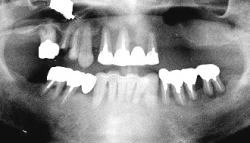

| 治療前 | 治療後 |

| 下顎の前歯部以外の全ての歯にグラツキがあったため、上顎はAll-on-4、下顎の奥歯は通常のインプラントブリッジとしました。 | |